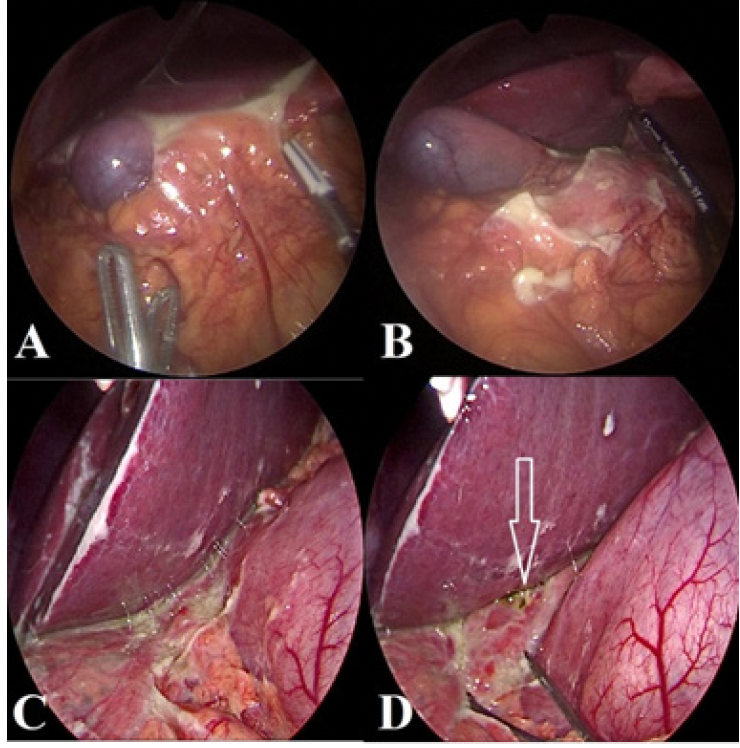

A total of 6 patients are enrolled in the study. All patients were males, and the median age of the patients was 16,65 years (range: 13-27 years ). All patients were admitted with abdominal pain lasting for no more than 4 days. Clinically, physical examination findings suggested acute appendicitis (tenderness/guarding/ rebound at the right lower quadrant) in all of the patients, and all underwent abdominal exploration for suspected acute appendicitis, but were finally concluded as Valentino’s Syndrome. In 1 patient with free air on plain X-ray examination (Figure 1), Valentino’s Syndrome was suspected before the operation and confirmed with laparoscopic exploration (Patient no:5). The duodenal perforation was possibly healed as no leak was observed after freeing the para-duodenal adhesions and air leak test was performed through the nasogastric tube. All patients had turbulent fluid in the pelvis and right paracolic gutter, but appendix vermiformis appeared as ‘innocent’ and was not perforated or inflamed enough to be the cause of turbulent fluid (Figure 2a-2d). Therefore, the attending surgeon urged to find the primary cause in all patients. Exploration of the whole abdomen was possible in 5 patients who underwent laparoscopic exploration but not in 1 patient who underwent open surgery. Periduodenal inflammation and omental adhesions were noticed in these patients (Figure 3a, 3b, 3c). When these adhesions were bluntly dissected, obvious duodenal perforation was visible in 2 patients (Figure 3d). The procedure was converted to open in these patients to repair the duodenal ulcer perforation. However, the adhesions on the duodenal wall were dense and dissection was challenging and regarded as hazardous in 3 patients, suggesting a chronic process and a possible healed perforation (Figure 3a and 3b). In the first case of these 3 patients, a simultaneous gastroscopy was performed during the operation, which demonstrated multiple duodenal ulcers, and integrity of the duodenal wall was confirmed (by air leak test and endoscopic vision). In the other 2 patients, a leak test was performed under laparoscopic vision by applying air through the NG tube. Appendectomy was performed in all these 3 patients due to the mystic nature of the condition, and the appendiceal lumen was found intact on histological examinations. No further action was performed, but all received medical treatment for duodenal ulcer until they had an elective gastroscopy. In 2 of these patients, intraperitoneal fluid was sampled intraoperatively for amylase and lipase levels with concomitant blood samples to compare with serum levels, and was found significantly higher. Intraperitoneal/serum amylase levels were 596/88 u/L and 150/59 U/L, lipase levels were 1551/29 U/L and 91/20 U/L. These findings are regarded as evidence of the duodenal origin of the intraperitoneal fluid. These 3 patients were subgroupped as Type B (occult, recovered, or healed duodenal perforation), and others were subgrouped as Type A (non-patent, disrupted duodenal wall).

Figure 2. Intraoperative findings in patients with Type B Val- entino’s. Relatively normal appearing appendix (A and D, yellow arrow), pelvic and paracaecal turbulent fluid (b and c), caecum (White star sign)

Figure 3. Paraduodenal adhesions and inflammatory changes in Type B (a) and Type A (c) Valentino’s Syndrome. After dissection of the adhesions, no opening was seen in Type B (b), but an obvious perforation in Type A (white arrow)(d)